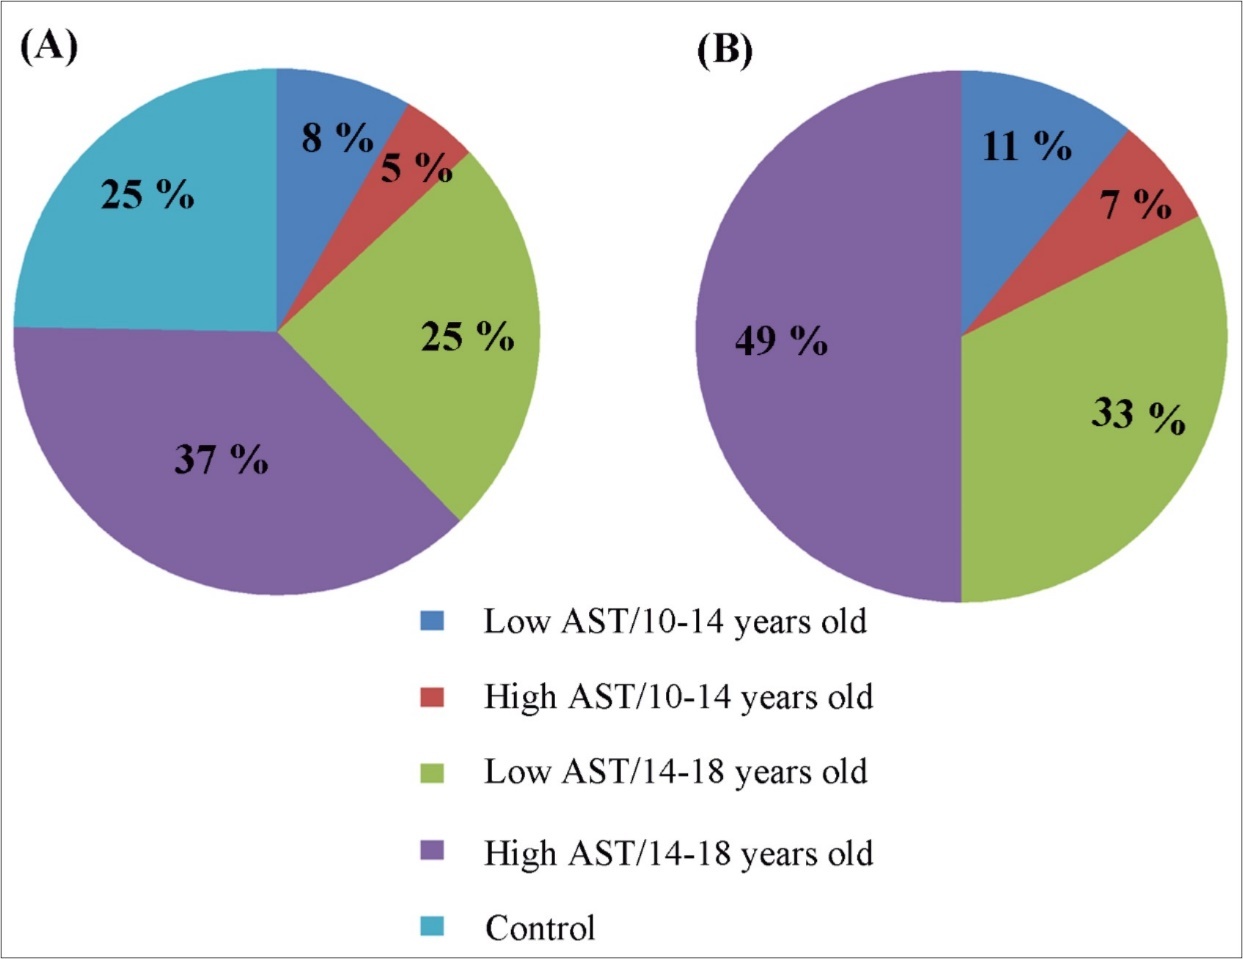

Sixty-nine 10-18year-old girls and boys participated in this study Fifty-two of the subjects had CD. Only six of them were girls, small female group, not statistically significant for comparison with the control group. Among forty-six AST boys, twenty boys were 10-14 years old and twenty-six were 14-18year-old (Figure 1A). The age and severity of CD (low vs. high) were explored only for boys. No signs of CD were found in seventeen boys and they formed the control group. Details on subject demographics and FPI assessment are summarized in Figure 1B.

Figure 1.Distribution (%) of subjects with antisocial tendencies (AST) by age and level of AST in (A) studied subjects and (B) the subjects with AST only. If the subject scores were up to three Freiburg Personality Inventory (FPI) scales above the normal range, he/she was considered with low AST. Higher scores in four and more FPI scales classified the child/youth with High AST.

The age and severity of CD (low vs. high) were explored only for boys, because the group size for girls with CD was small, this as limitation consequently, no gender effect was evaluated. The age and severity of CD (low vs. high) were explored only for boys.

(Figure 1) depicts the prevalence of low- and high-CD in studied subjects. Distribution (%) of subjects with CD tendencies by age and level of CD in (A) studied subjects and (B) the subjects with CD only.